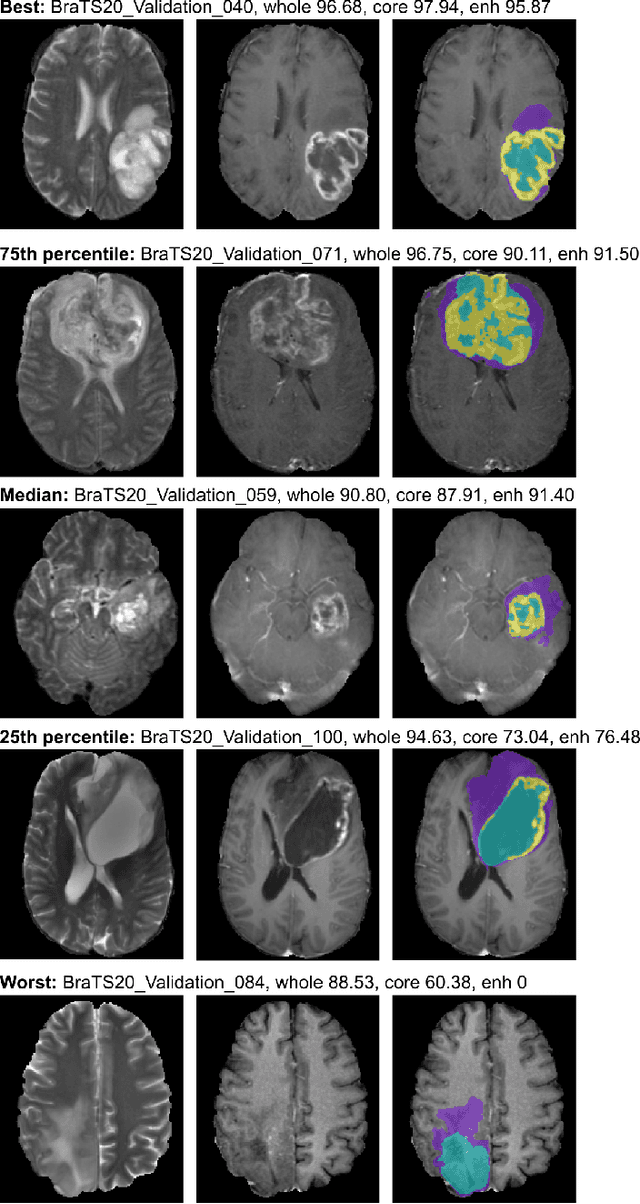

We apply nnU-Net to the segmentation task of the BraTS 2020 challenge. The unmodified nnU-Net baseline configuration already achieves a respectable result. By incorporating BraTS-specific modifications regarding postprocessing, region-based training, a more aggressive data augmentation as well as several minor modifications to the nnUNet pipeline we are able to improve its segmentation performance substantially. We furthermore re-implement the BraTS ranking scheme to determine which of our nnU-Net variants best fits the requirements imposed by it. Our final ensemble took the first place in the BraTS 2020 competition with Dice scores of 88.95, 85.06 and 82.03 and HD95 values of 8.498,17.337 and 17.805 for whole tumor, tumor core and enhancing tumor, respectively.